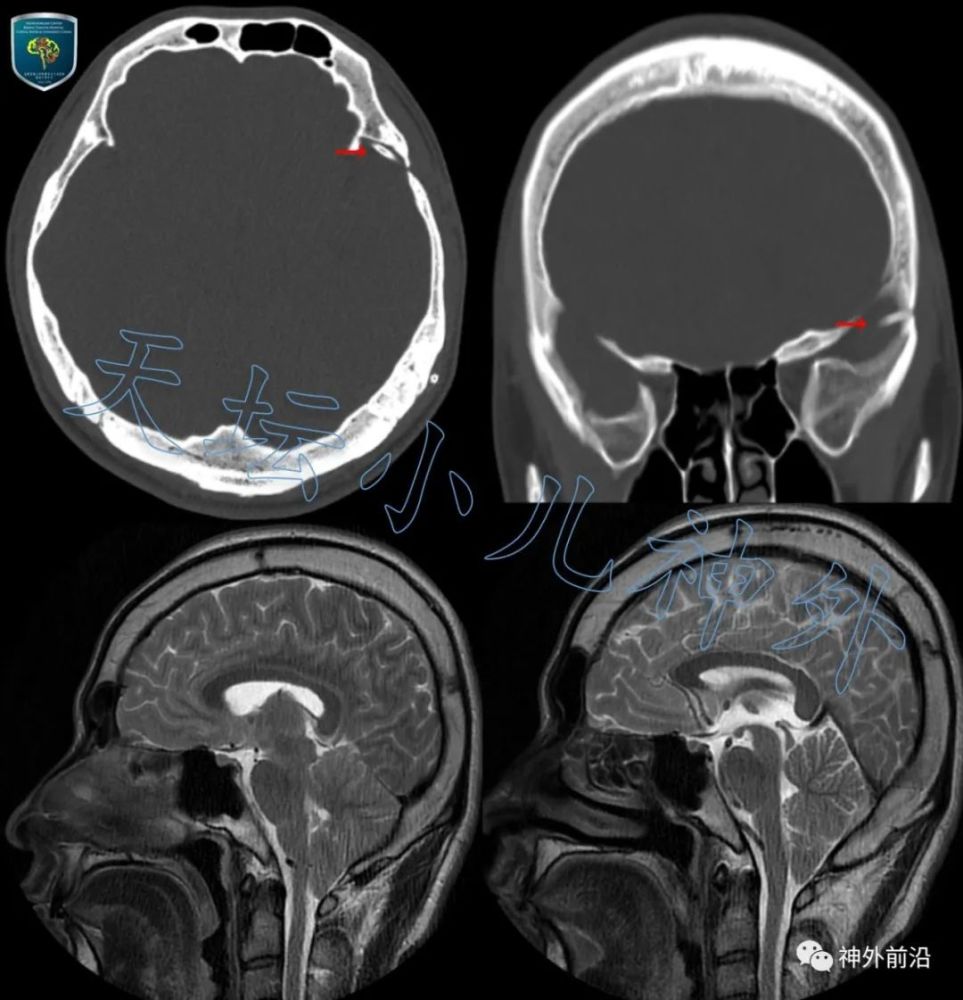

图1. 11岁男性患儿 , 主诉“左颞蛛网膜囊肿-腹腔分流术后9年 , 间断性头痛1月进行性加重 , 恶心呕吐4天” 。 头颅CT显示:双侧脑室裂隙状缩小 , 箭头指示分流管囊肿端已堵塞 。